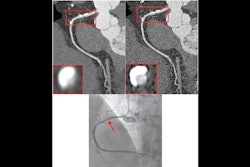

Froemming also recognized literature that supports the value of PCCT for cardiovascular applications, and stressed that it is important to allocate resources where PCCT leaves "no operational white space."